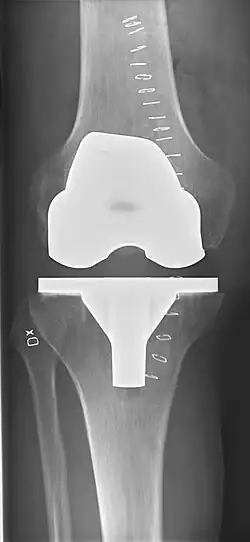

El reemplazo de rodilla se evalúa de forma rutinaria mediante rayos X, incluidas las siguientes medidas:

-

CRT: Ángulo cadera-rodilla-tobillo, que idealmente está entre 3° en varum y 3° en valgum desde un ángulo recto.[54] -

- CFF: ángulo del componente femoral frontal. Por lo general, se considera óptimo cuando se encuentra entre 2 y 7° en valgo.[55]

- CTF: ángulo del componente tibial frontal, que se considera óptimo cuando se encuentra en ángulo recto. En general, se ha encontrado que una posición en varo de más de 3 ° aumenta la tasa de falla de la prótesis.[55] -

- La entalladura femoral anterior (el componente femoral que causa una reducción del grosor del fémur distal en la parte anterior) parece aumentar el riesgo de fracturas cuando excede aproximadamente 3 mm.[56]

- CTL: ángulo del componente tibial lateral (o sagital), que está idealmente posicionado de modo que la tibia esté flexionada de 0 a 7° en comparación con un ángulo recto con la placa tibial.[55]